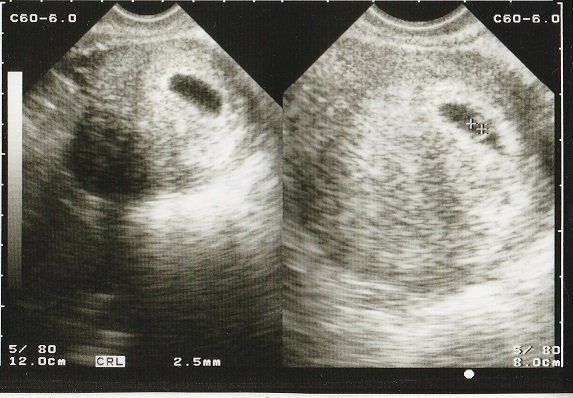

妊娠4週目 初めてのエコー画像

結婚10年目にしてやってきた待望の赤ちゃん。初めてのエコー画像は「ここに本当に赤ちゃんがいるの?」というようなものでした。初期の流産を経験しているので、「何かあったらすぐに連絡するように」と、当時は主治医の先生の携帯番号がエコー写真の下に添えてありました。

妊娠5週目のエコー写真 胎嚢が見える

胎嚢(赤ちゃんがはいった袋)が確認できるようになりました。

妊娠6週目のエコー写真 胎芽が見える

胎嚢が大きくなり、そのなかに胎芽(7週未満の赤ちゃん)が確認できるようになりました。